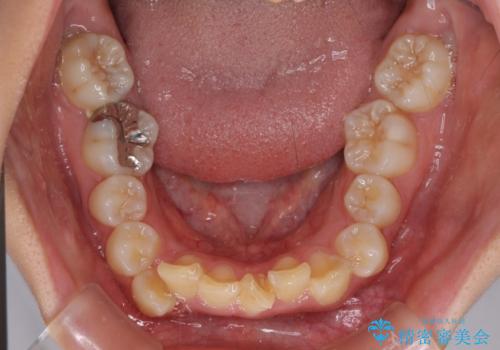

- 前方に飛び出した前歯と、下顎の八重歯を気にして来院された患者様です。

口元の突出感を改善するため、上下左右の第一小臼歯4本を抜歯し、ワイヤー装置にて矯正治療を行うこととしました。